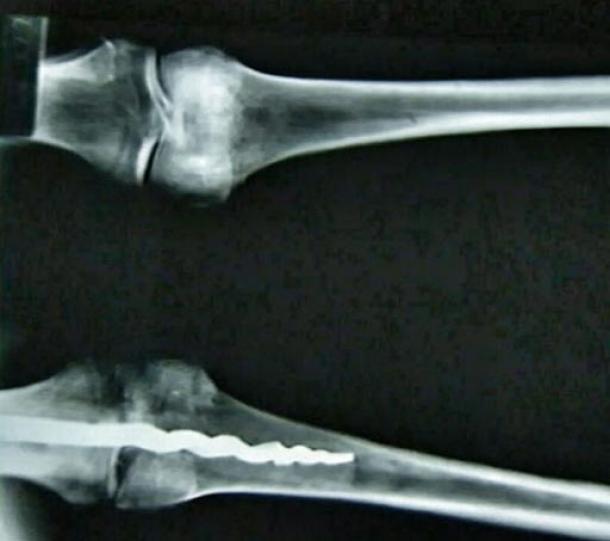

Xác ướp Usermontu và ảnh X quang chụp cái đinh ốc (ảnh: Wiki, GS. Griggs ĐH Brigham Young)

Hai thập kỷ sau, một nhóm các nhà khoa học đã phát hiện sự thật gây chấn động – xác ướp ẩn chứa bên trong bằng chứng về một ca phẫu thuật tiên tiến được thực hiện gần 2.600 năm trước đây. Bên trong đầu gối trái của xác ướp là một đinh ốc kim loại chỉnh hình dài 23cm, được đưa vào bằng những thủ thuật cơ sinh học vô cùng tiên tiến không thua kém gì kỹ thuật hiện đại hôm nay.

Tháng 8 năm 1995, Giáo sư C. Wilfred Griggs thuộc trường Đại học Brigham Young, bang Utah Hoa Kỳ và một nhóm các chuyên gia khác, đã tiến hành chụp X-quang 6 xác ướp được lưu trữ tại Bảo tàng Rosicrucian, trong đó có xác ướp Usermontu, trước khi ông tổ chức giảng bài tại đây. Họ đã rất sốc khi những thước phim cho thấy một chiếc đinh vít bằng kim loại dài 23cm nằm trong đầu gối trái của một xác ướp.

Theo báo cáo của BYU, chiếc đinh vít “xuyên vào xương đùi theo cấu trúc hình xoắn ốc, tương tự như phương pháp cơ sinh học đang sử dụng hiện nay. Đầu còn lại của đinh vít nằm trong xương chày, có ba gờ nổi vươn ra khỏi thân của chiếc đinh để ngăn chiếc đinh tự xoay trong xương.”